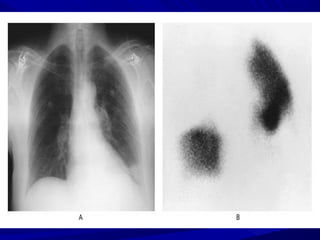

V/Q scanningV/Q scanning

Look for evidence of ventilation perfusionLook for evidence of ventilation perfusion

mismatchmismatch

Can only really be done if pt has normal CXRCan only really be done if pt has normal CXR

Normal scan virtually excludes PE even ifNormal scan virtually excludes PE even if

pretest clinical probability was felt to be high.pretest clinical probability was felt to be high.

If a patient with intermediate clinical probabilityIf a patient with intermediate clinical probability

of PE has an intermediate scan then needof PE has an intermediate scan then need

further testingfurther testing